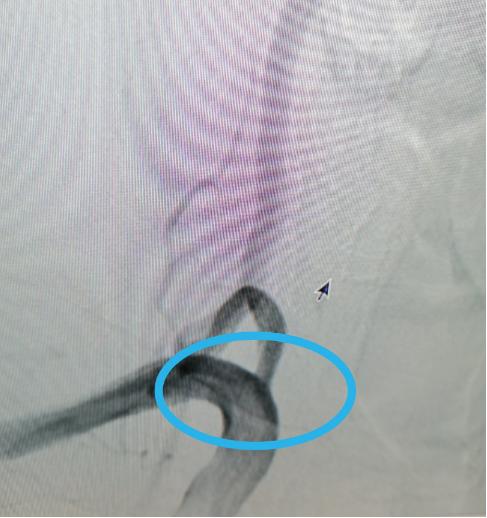

术后↑:支架植入后,狭窄缓解,造影显示椎动脉通畅

在征得齐大爷及家属同意后,手术由四川大学华西医院神经外科介入专家张昌伟教授、区人民医院神经外科副主任医师任飞亚共同进行,约1小时后,手术顺利完成。术后,齐大爷的症状得到明显改善,恢复良好,三天不到就出院了。

这种病症的主要原因是由椎动脉狭窄引起,为此,在治疗上必须对症下药才能解决齐大爷的顽疾。综合考虑到患者年龄、身体状况、恢复情况和治疗效果等方面,科室团队为齐大爷制定了详细的治疗方案,决定采取 微创手术治疗——椎动脉狭窄球囊扩张支架植入术 。